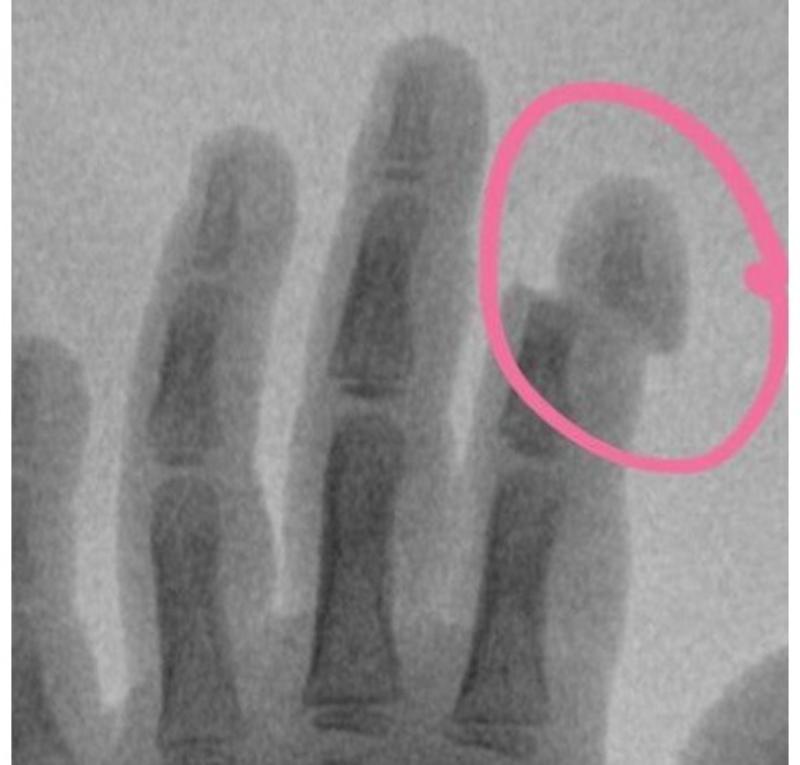

5-летняя девочка поступила с травмой указательного пальца в Московскую областную детскую клиническую травматолого-ортопедическую больницу (МОДКТОБ): ногтевая фаланга буквально держалась за счет кожи.

5-летняя девочка поступила с травмой указательного пальца в Московскую областную детскую клиническую травматолого-ортопедическую больницу (МОДКТОБ): ногтевая фаланга буквально держалась за счет кожи. Как выяснилось, травму маленькая пациентка получила из-за детской коляски, ее механизм буквально «отщелкнул» палец, сообщает пресс-служба регионального Минздрава.

«Специалистами больницы проведены ревизия раны, артропластика – хирургическая процедура, необходимая для восстановления функции сустава. Кроме того, была проведена пластика сухожилия разгибателя и восстановлены сосуды. Данная травма крайне тяжелая и сопряжена с длительным реабилитационным периодом. Конечный результат операции и объем восстановления после травмы будет виден нескоро, поэтому пока все зависит от организма ребенка и его способности к восстановлению. К счастью, детский организм имеет неисчерпаемые возможности и способен к регенерации», - рассказал Григорьев Александр Владимирович главврач медучреждения и главный внештатный детский специалист травматолог-ортопед Минздрава Московской области.